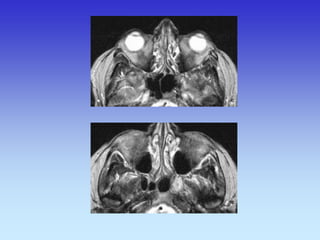

CT- ORBITA

TRANSVERZALNI SLOJ

ORBITE